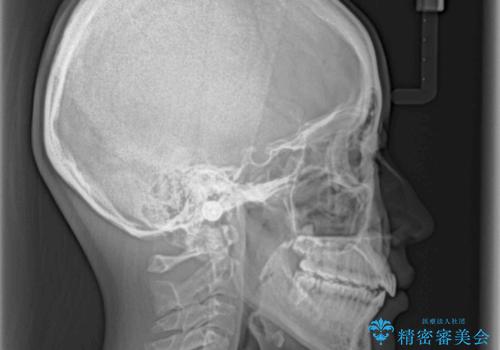

オープンバイトのインビザラインを用いた再矯正

- 矯正治療の後戻りを気にして来院された患者様です。

オープンバイト(前歯の開咬)と下顎骨の偏位による不正咬合が認められました。

骨格の偏位による不正咬合は改善しきれないことを理解いただいた上で、インビザラインにて矯正治療を行うこととしました。

オープンバイトは後戻りを起こしやすいため、極力そのリスクを軽減するため、奥歯を圧下させるように治療を進めていきました。

下顎骨の偏位が顕著であったため、上下の正中を合わせることはできませんでしたが、患者様には大変満足していただきました。